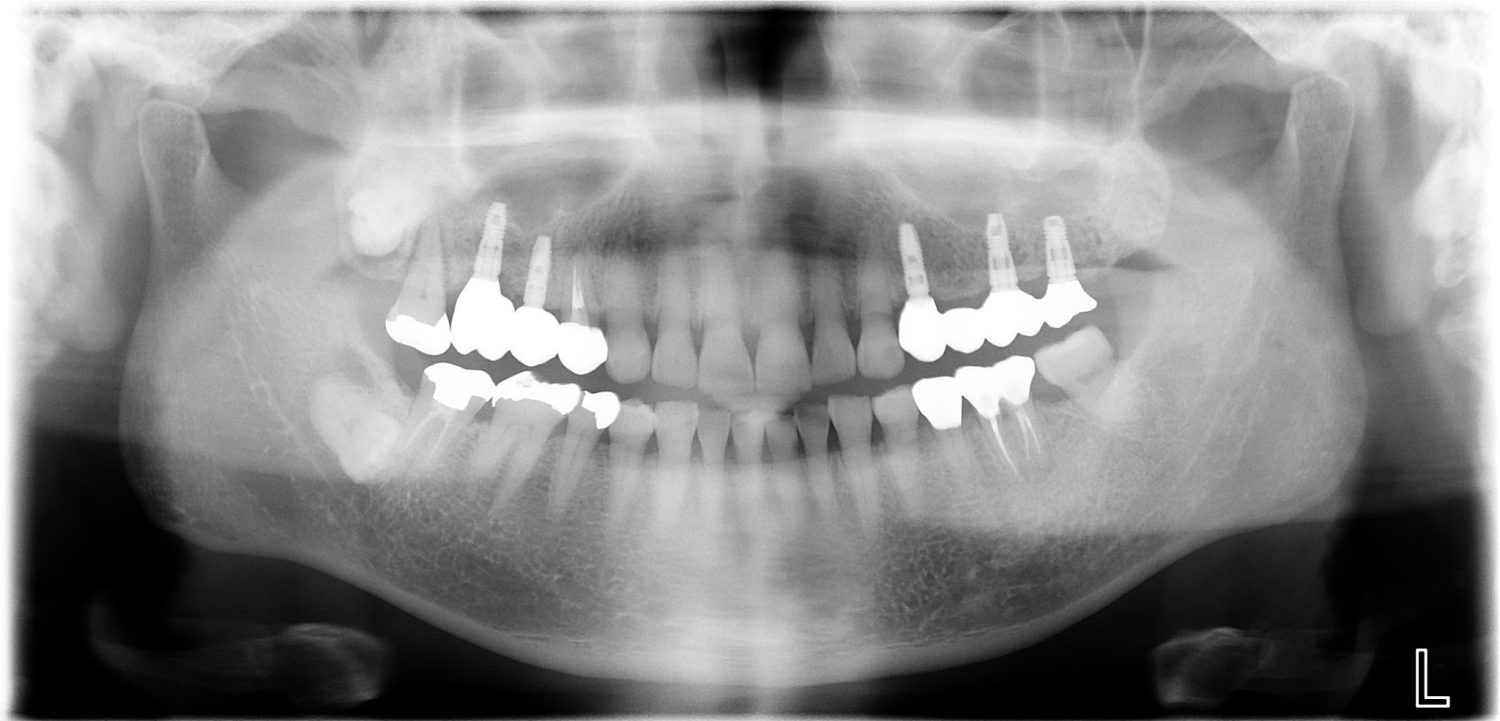

インプラント治療の症例紹介③

Before

After

治療内容

保存不可能な歯の抜歯

下顎にインプラント埋入し咬合再構成

多数歯う蝕および多数歯欠損による咬合崩壊、保存不可能な歯の抜歯により上下無歯顎に。下顎に6本インプラント埋入する事で咬合再構成を行った。